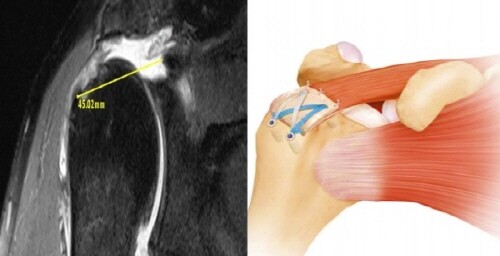

또한 이식술이라고 해서 장기이식처럼 큰 수술이 아니라 평균 10~15분 정도의 과정만 추가된다. 수술 과정은 영상의학 검사를 통해서 변성, 소실된 결손 부위를 계측한 다음 이에 맞는 동종진피를 제작한다.

수술에 들어가면 동종진피를 결손부위에 덧대주는 10~15분 내외 1차 봉합술을 한 뒤 장력의 정도를 확인하고 나서 2차로 일반파열 환자와 마찬가지로 브릿지이중봉합술을 시행하는 것으로 수술을 마치게 된다.